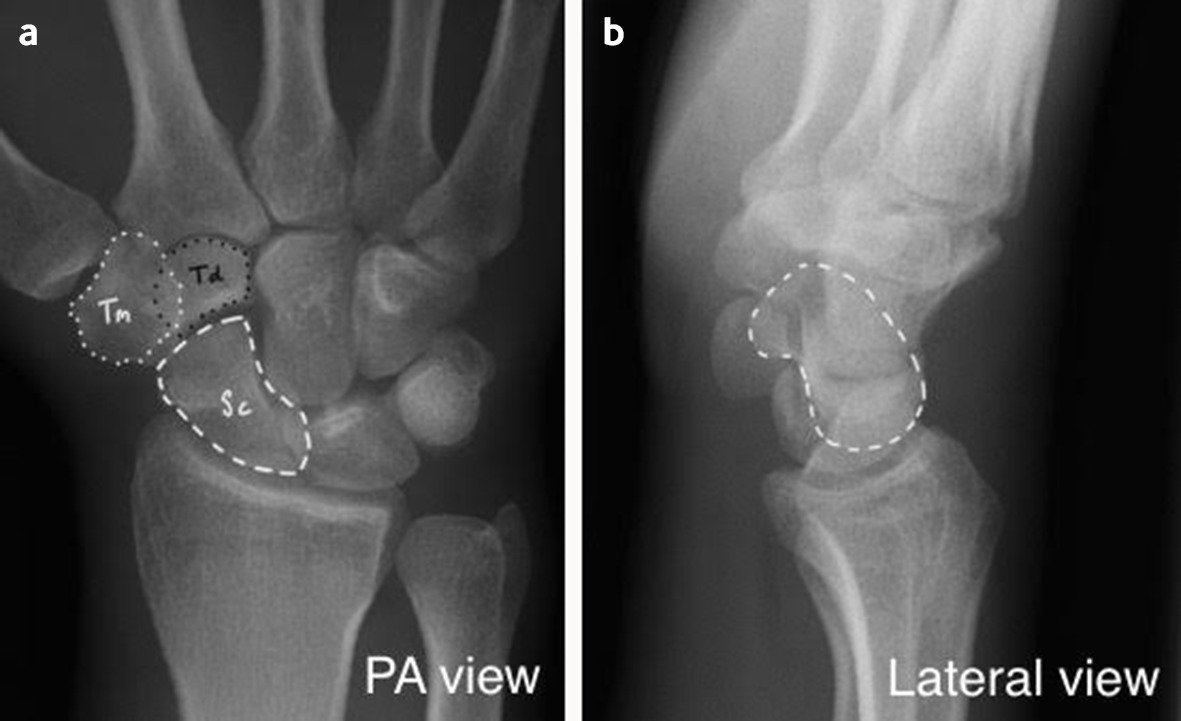

Scaphoid fracture. (a) PA radiograph of the right wrist with ulnar Scaphoid Fracture X Ray Oblique Plain radiographs taken soon after the injury may not reveal a fracture, but the clinician should assume one is present until. Scaphoid fractures are the most common carpal bone fracture, often occurring after a fall onto an outstretched hand. Often if a scaphoid fracture is suspected and not. Scaphoid fractures are the second commonest group of fractures that are seen. Scaphoid Fracture X Ray Oblique.